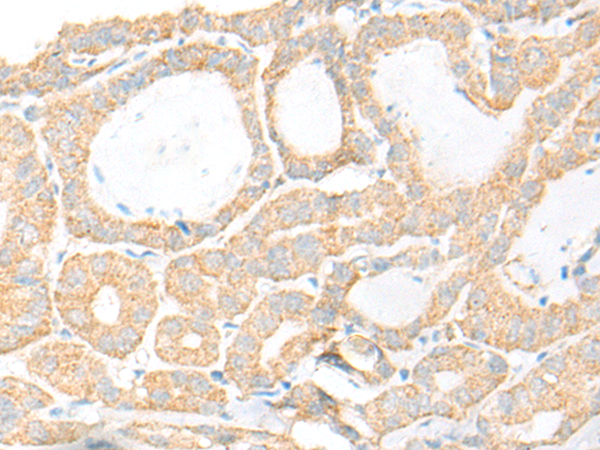

分类: 科研抗体货号: P06307别名: SUR2; CRSP3; MRT18; SUR-2; ARC130; CRSP130; CRSP133; DRIP130应用: IHC反应种属: Human, Mouse, Rat